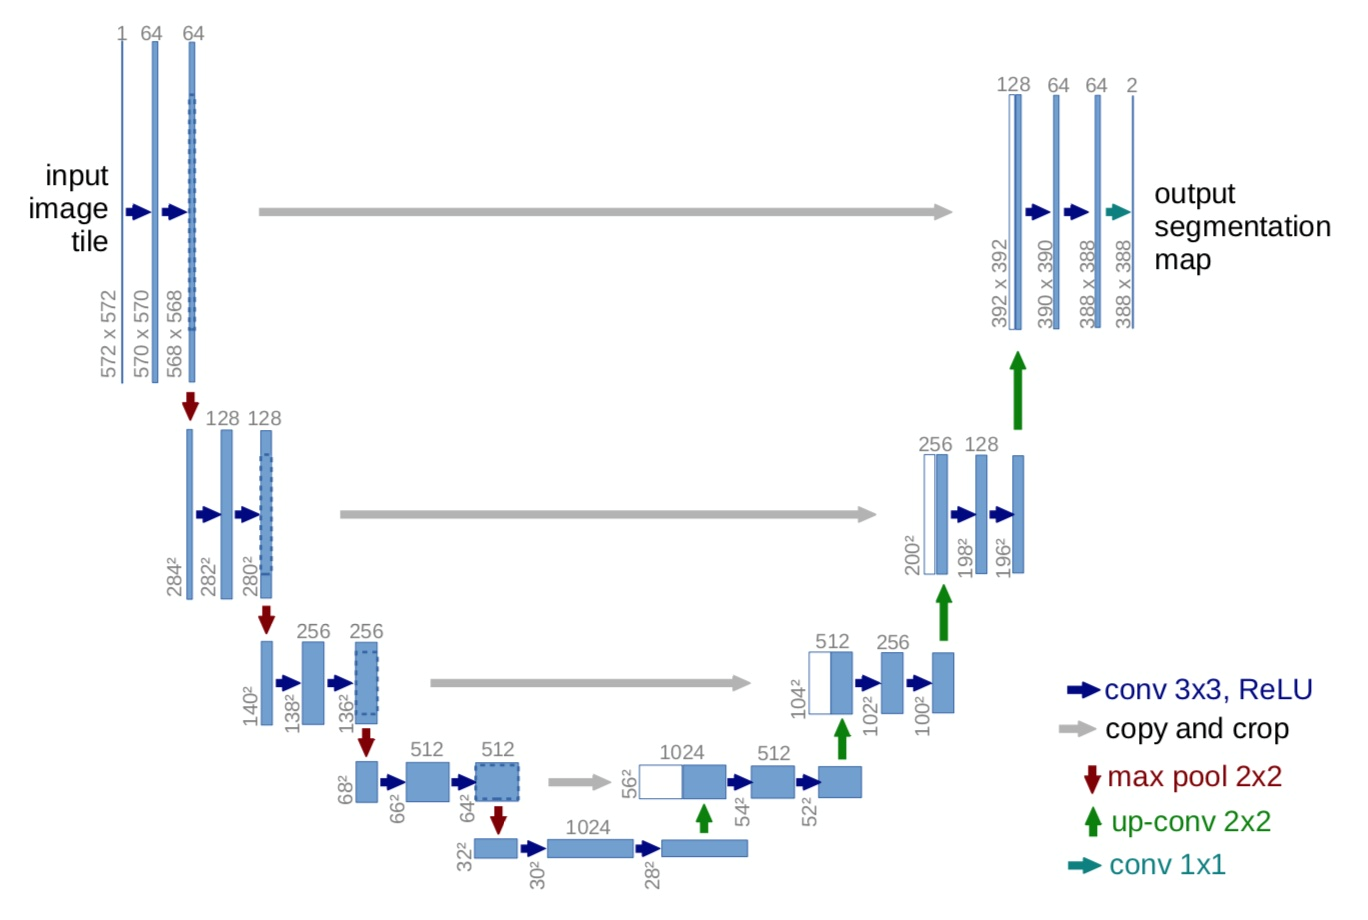

6.3.5.1 结构

一个contracting path即收缩路径(左侧)和一个expansive path即扩展路径(右侧)组成。

- 1、收缩路径遵循卷积网络的典型架构。它包括重复使用两个3x3卷积(无填充卷积),每个卷积后跟一个线性修正单元(ReLU)和一个2x2最大池化操作,步长为2的下采样。

- 在每个下采样步骤中,我们将特征通道的数量加倍。

- 2、扩展路径中的每一步都包括特征映射的上采样

- 1、进行2x2卷积(“反卷积”),将特征通道数量减半,与来自收缩路径的相应裁剪特征映射串联

- 2、然后是两个3x3卷积,每个卷积后面接ReLU。

- 由于每一次卷积都会丢失边界像素,因此裁剪是必要的。在最后一层,使用1x1卷积将每个64分量特征向量映射到所需数量的类别上。

- 3、网络采样细节

- UNet的encoder下采样4次,一共下采样16倍,对称地,其decoder也相应上采样4次,将encoder得到的高级语义特征图恢复到原图片的分辨率。网络较小运行速度快

图中箭头解释:

* 每一步都首先使用反卷积(up-convolution),每次使用反卷积都将特征通道数量减半,特征图大小加倍。(绿箭头)

* 反卷积过后,将反卷积的结果与contracting path中对应步骤的特征图拼接起来。(白/蓝块)

* contracting path中的特征图尺寸稍大,将其修剪过后进行拼接。(左边深蓝虚线)

* 对拼接后的map再进行2次3*3的卷积。(右侧蓝箭头)

* 最后一层的卷积核大小为1*1,将64通道的特征图转化为特定类别数量(分类数量,二分类为2)的结果。(青色箭头)